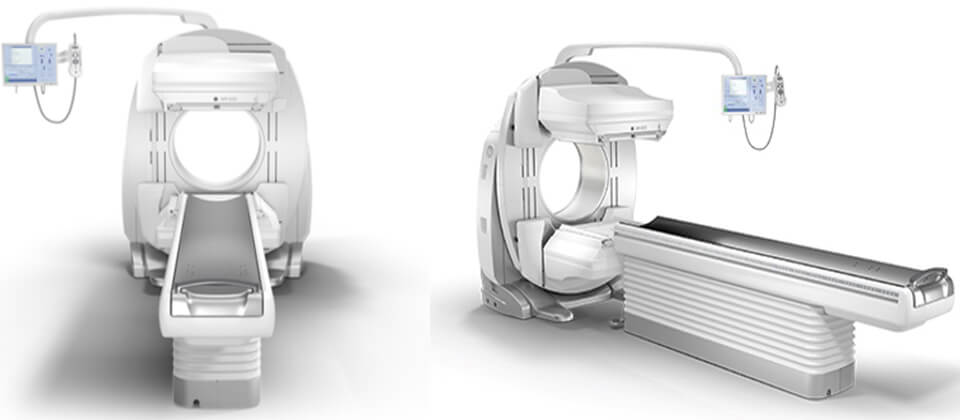

核医学検査部⾨

核医学検査とは、放射性同位元素(Radio Isotope)を⽤いて⾏う検査です。体内にRIを含む薬剤を投与(経⼝もしくは静脈注射)する事で、全⾝へと運ばれ、特定の臓器や組織に取り込まれて集積します。

これを特殊な撮像装置(ガンマカメラ)を利⽤して、放出される放射線(主にガンマ線)を検出することで臓器や組織の形状・機能を調べます。

注射後、⽬的の臓器や組織に薬剤が集積するまで約3時間を要する検査や数⽇かかる検査もあります。検査は装置のベッド上で安静状態の寝た体勢で⾏います。撮影時間は30分〜1時間程度です。

検査に⽤いる放射性医薬剤は⼈⼯的に作られたもので、副作⽤はほとんどありません。体内に⼊った薬剤からは放射線が出ますが極微量で、検査を受ける本⼈や周囲の⼈々への影響について⼼配はありません。検査も苦痛なく⾏えるのが特徴です。

核医学検査に⽤いる薬剤のほとんどは尿・便排泄されます。また、放射線の量は時間とともに減少していくので、後々まで体内に残って放射線が出ることはありません。

ガンマカメラ(GEヘルスケア NM830)

ガンマカメラ(GEヘルスケア NM830)

当センターでは、主に⾻シンチグラフィ、⼼筋(負荷・安静)シンチグラフィ、脳⾎流シンチグラフィの検査を⾏っています。そのほかにも、甲状腺シンチグラフィや腎動態シンチグラフィなど多種多様な検査の受け⼊れ態勢も整っています。